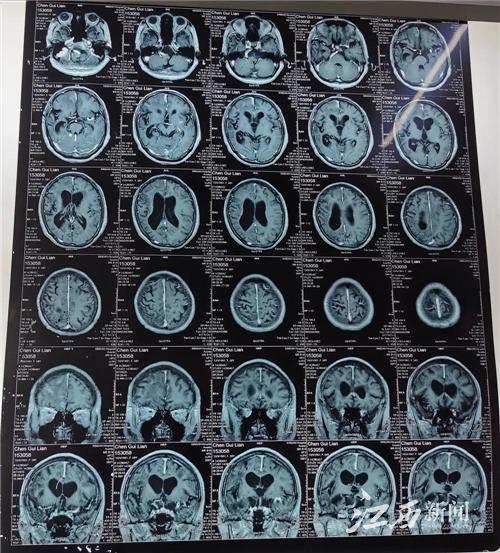

接診的徐春華聽了癥狀描述后,立刻安排她做了進一步磁共振檢查和腦電圖檢查,發現顱內右側額葉有多個明顯的寄生蟲肉芽腫病灶,癲癇放電也來自右側前頭部。

圖為2020年術前頭顱磁共振片

徐春華介紹,大腦受到散在多發的寄生蟲病灶刺激和破壞,是引起癲癇發作的主要原因。